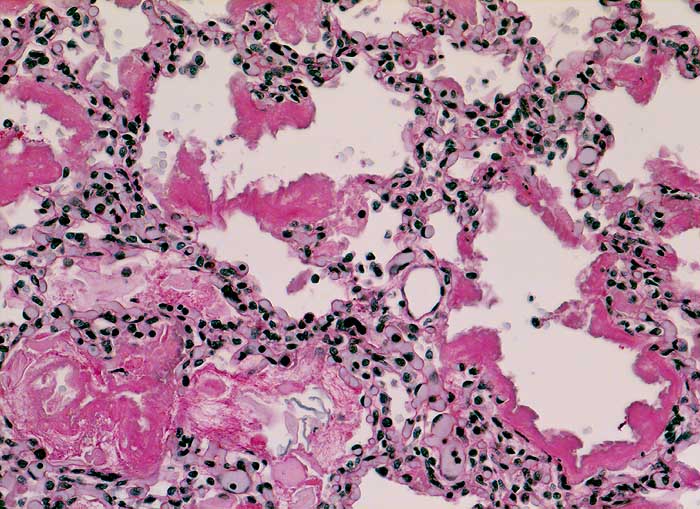

PathoPic ID 6177 - Hyaline Membranenkrankheit (IRDS)

Hyaline Membranenkrankheit (IRDS)

Massive Mekoniumaspiration:

Mekonium in einzelnen Alveolarräumen. Die Alveolarsepten sind austapeziert von PAS positiven

hyalinen Membranen.

Normalgewichtiges Neugeborenes der 37. SSW. Linksbetonte Hypoplasie beider Lungen. Lungen vor allem im alveolären Stadium.

Kongenitale beidseitige Diaphragmahernie bekannt seit 24. Schwangerschaftswoche.

Asphyxie bei Hypoplasie beider Lungen.

Histologie

Vergrösserung